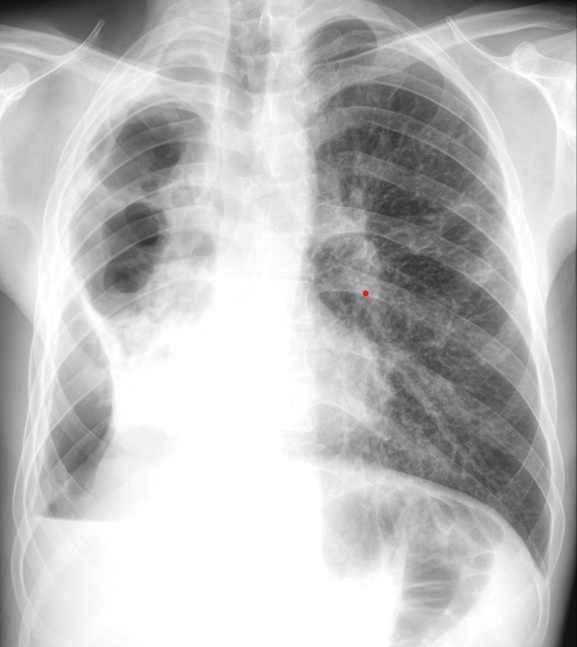

Aceasta susține că numărul cazurilor de tuberculoză a scăzut cu 69% în ultimele două decenii, iar profilul epidemiologic istoric al României se prezintă astfel: 85% tuberculoză pulmonară și 15% tuberculoza extrapulmonară.

În Galați, în 2024 au fost 224 de cazuri, iar în 2025 s-au înregistrat 210 cazuri de tuberculoză. La copii, în 2024, au fost 11 cazuri, iar în 2025 au fost 13 cazuri, fiind întâlnite forme de tuberculoză specifice adultului (forme infiltrative și cavitare).

Se menține tendința globală și națională de scădere a numărului de cazuri de tuberculoză. „Formele sunt însă mai grave, cu distrucții importante ale plămânilor, deoarece prezentarea la medic este întârziată (de teamă, din motive financiare etc). Profilul anterior de pacient: tânăr, cu puține boli asociate, tratament cu rezultat previzibil. Profilul prezent de pacient: vârstnic sau de vârstă medie, cu multiple comorbidități (diabet, boli cardiace, renale, neoplazice), aderentă scăzută la tratament. Comorbiditățile pacientului întârzie diagnosticul și îl îngreunează, riscul de eșec terapeutic fiind crescut şi apărând recăderea”, a mai spus dr. Marta Lefter.